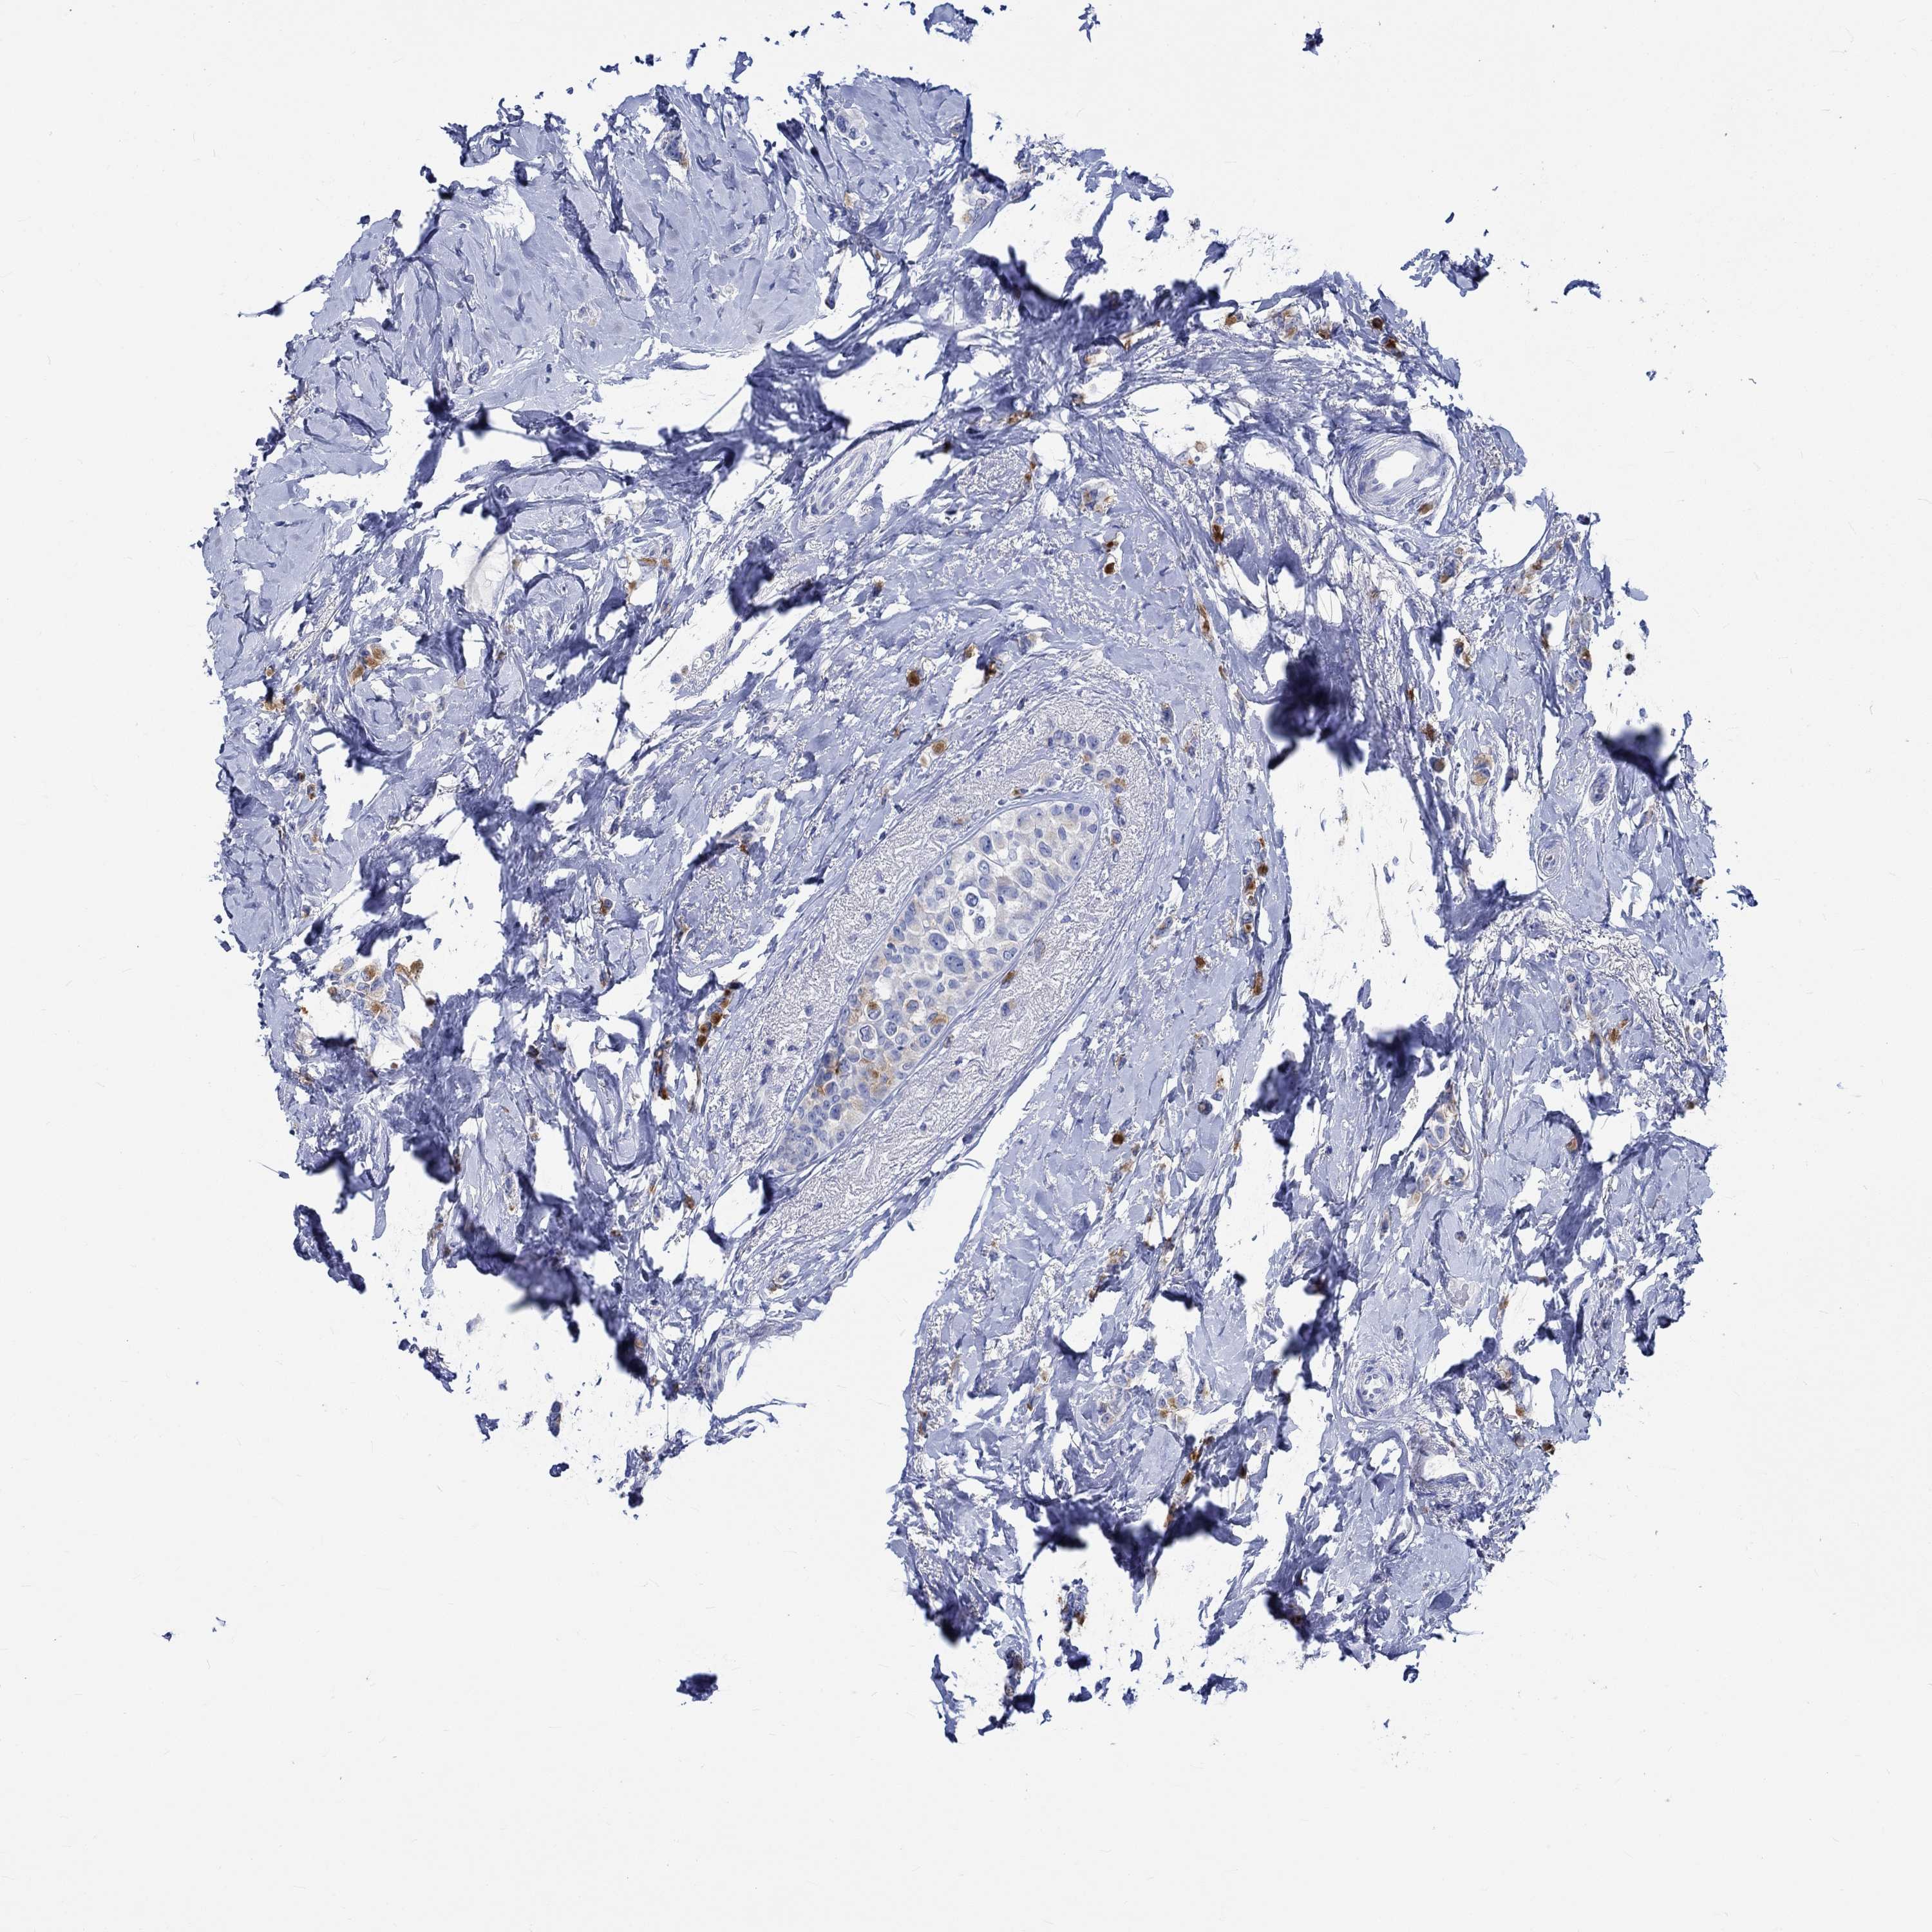

CANCER BREAST CANCER Show tissue menu

BRCA TCGA BRCA VALIDATION PROTEIN EXPRESSION